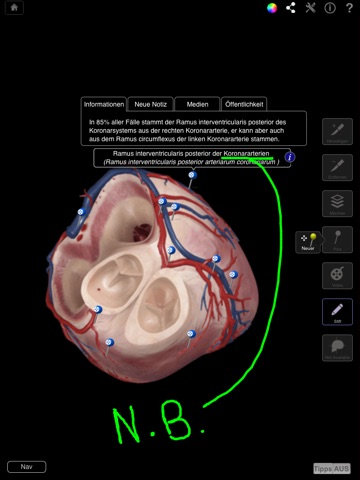

• Zeichnen Sie auf einer beliebigen Ansicht ein Bild und teilen Sie es über E-Mail, Facebook oder Twitter.

• Öffentliche Anmerkungen: Posten Sie neue Anmerkungen oder blättern Sie durch geteilte, öffentliche Anmerkungen.

• Anpassbare Pins - Sie können eigene Pins und Anmerkungen erstellen oder Anmerkungen zu vorhandenen Pins hinzufügen.